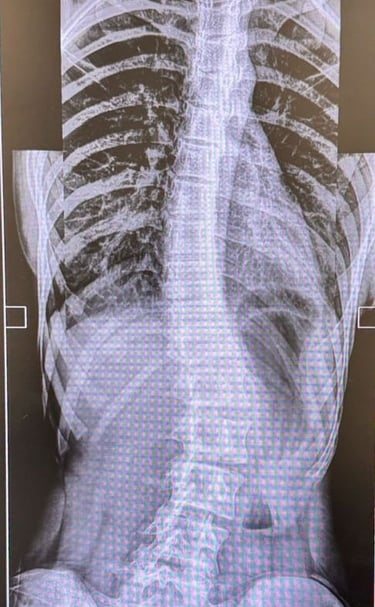

Scoliosis Care

When in doubt about curvatures in your spine - consult doctor to asses the curvatures, plan management.

Gallery

Explore our advanced spine care visuals.